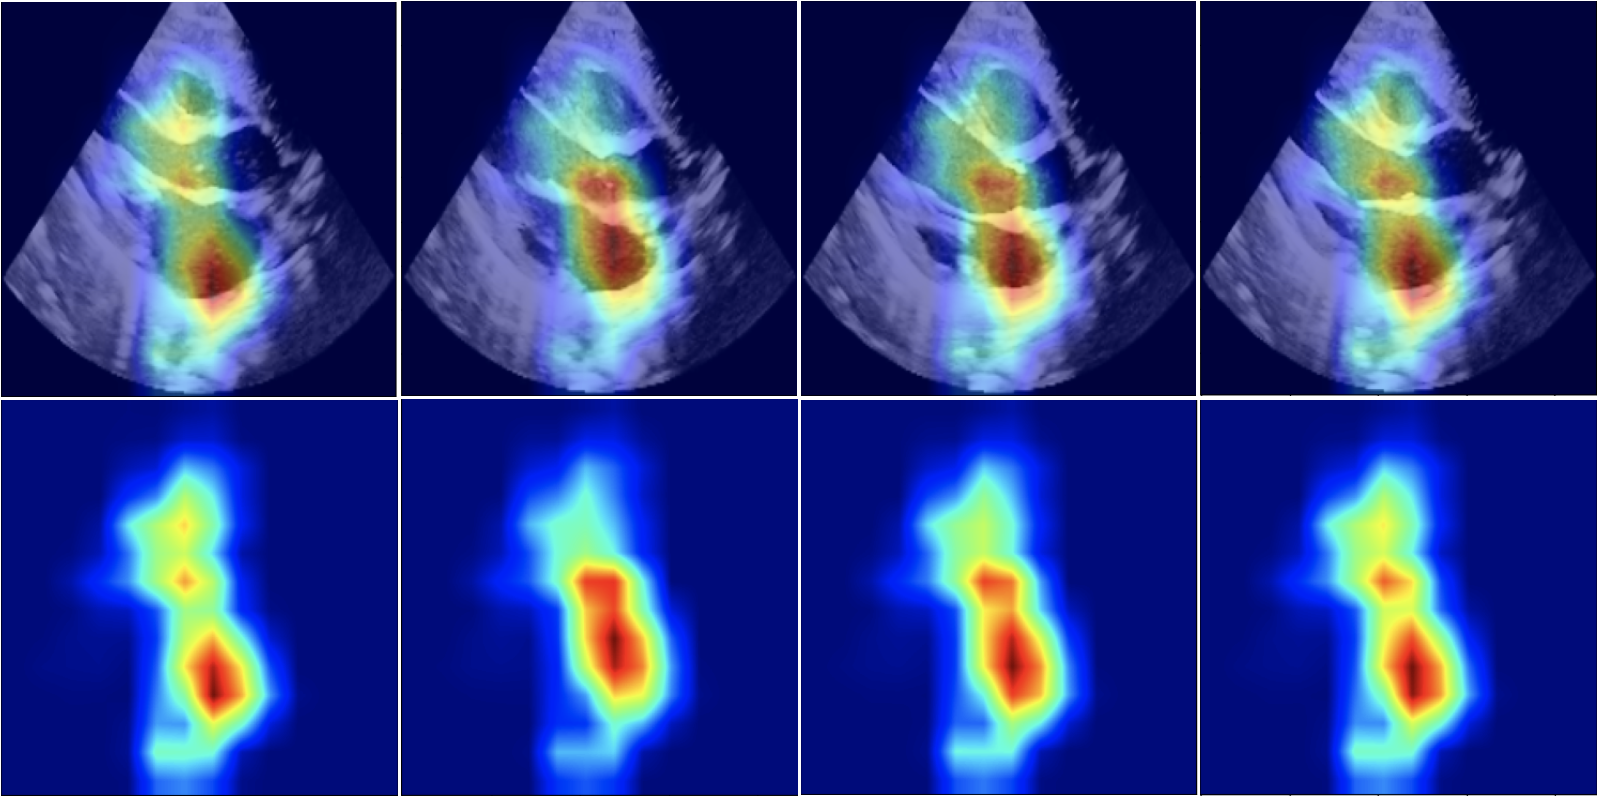

Note that, for simplicity, we show the visualisation results of a single frame per patient in Fig. 2. In a clinical setting, the visualizations can be viewed as a video containing spatio-temporal explanation. In Supplementary Material, we show more examples of how the focus changes along the frames of a sequence.

Refer to caption

Figure 3: Spatio-temporal Grad-CAM saliency maps (bottom) imposed on the original frames (top) for frames corresponding to systole, mid, diastole, mid in a PLAX ECHO.